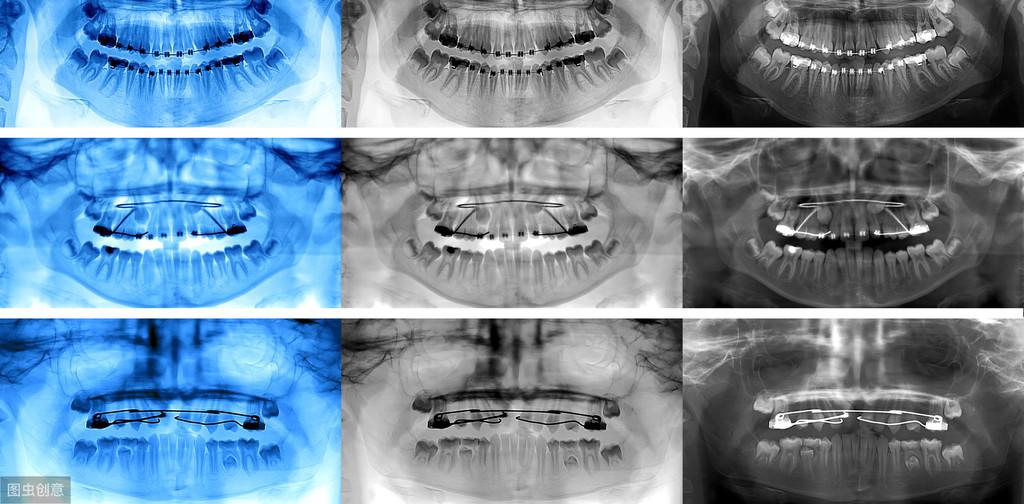

牙齒種植術(shù)是目前好的缺失牙齒修復(fù)技術(shù)之一,因?yàn)樗姆N植技術(shù)是通過手術(shù)將種植體植入到牙槽骨里,獲得了骨組織的固位支持,所以種植牙齒的穩(wěn)定性、性和使用年限都高,因此,種植牙從發(fā)展到現(xiàn)在也獲得了醫(yī)學(xué)界專家廣泛的認(rèn)可和大量有需要患者的喜愛。

我是牙科醫(yī)生黃征難,36年從業(yè)經(jīng)歷,如果你有任何口腔問題,歡迎關(guān)注后在主頁(yè)私信咨詢,或評(píng)論留言!可以私信牙片,我來幫你免費(fèi)問診!拓展知識(shí):瑞士種植牙系統(tǒng)多少錢一個(gè)